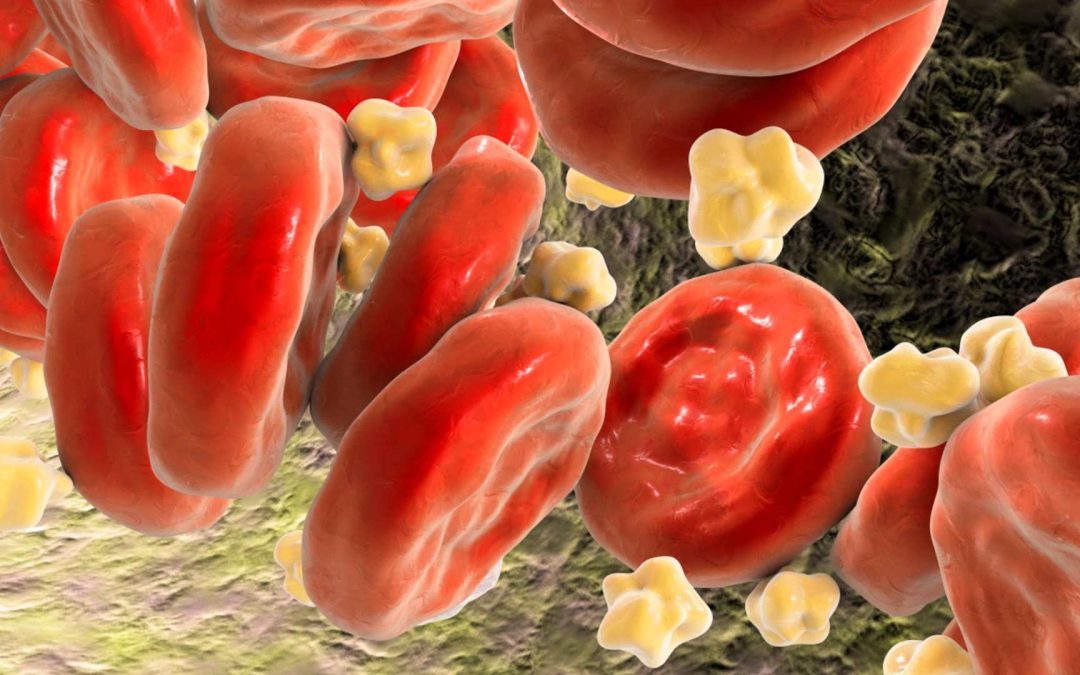

Holesterol je naš prijatelj – 1. del

Pa začnimo z nekaj preprostimi dejstvi, ki jih lahko najdete na straneh vseh laboratorijev in klinik. Bolezni srca in ožilja so vodilni vzrok smrti in umrljivosti po vsem svetu. Kardiovaskularne bolezni vključujejo širok spekter bolezni, ki...